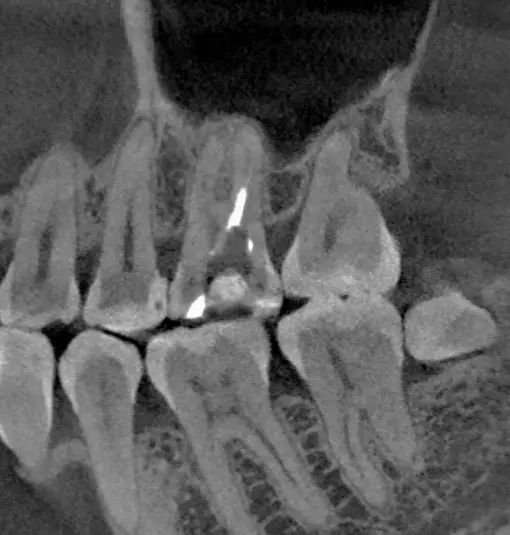

TOMOGRAFÍA PARA ENDODONCIA

Evaluación necesaria en campo reducido para visualizar los conductos radiculares o probables fracturas.